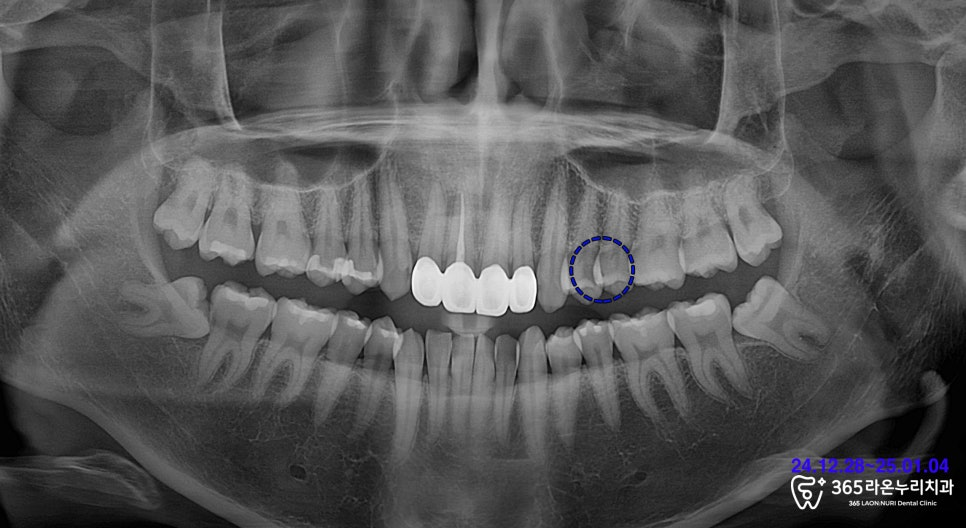

엑스레이 촬영 및

위턱의 진단을 통해

상아질 우식(충치)을 의심할 수 있었습니다.

그래서 세마동 치과 에서는

교익 촬영 후 충치의 진행

정도를 확인해보았는데요.

음식을 먹는 곳인

교합면의 2/3 정도가

썩어버리고 말았습니다.

그렇게 인레이 진단을

내려드렸습니다.